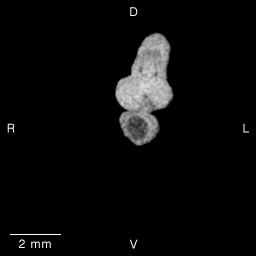

Stage 14 (Day 32), transverse slice 12